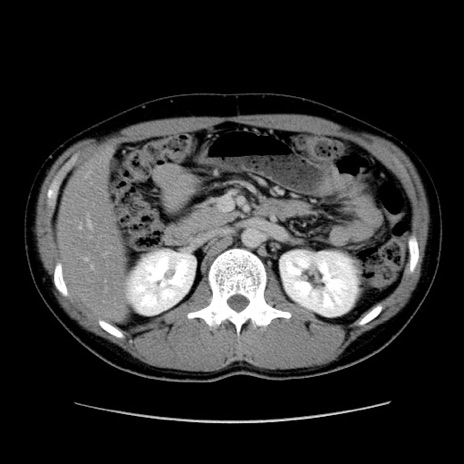

症例36(横断像)

【症例】20歳代 男性

【主訴】心窩部痛

【現病歴】今朝より上腹部痛あり。一旦軽快していたが再度出現したため救急要請。昨日夕に白身の魚を含む刺身を食べた。

【身体所見】BP 136/89mmHg、HR 74/min、BT 37.0℃、腹部:膨満、軟、心窩部に圧痛あり。反跳痛なし、筋性防御なし、腸雑音やや亢進あり。

【データ】WBC 17700、CRP 0.48